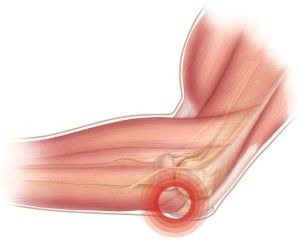

Рука вільно згинається в лікті завдяки присутності спеціальної навколосуглобових сумки під назвою бурса.

В її порожнини є трохи рідини, яка виступає в якості мастила, тим самим зменшуючи тертя і попереджаючи різні мікротравми.

Коли виникає запалення суглобової сумки, то прогресує бурсит. Успішне лікування бурситу ліктьового суглоба в результаті повертає кінцівкам рухливість.

Бурсит ліктя називається процес запалення в синовіальних сумках, що оточують суглоб.